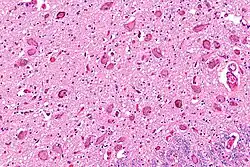

The locus coeruleus is affected in many forms of neurodegenerative diseases: genetic and idiopathic Parkinson's disease, progressive supranuclear palsy, Pick's disease, and Alzheimer's disease. It is also affected in Down syndrome.[29] For example, there is up to 80% loss of locus coeruleus neurons in Alzheimer's disease,[30] Mouse models of Alzheimer's disease show accelerated progression after chemical destruction of the locus coeruleus.[31] Neurofibrillary tangles, a primary biomarker of Alzheimer's disease, may be found in the locus coeruleus decades before any clinical symptoms.[32] The norepinephrine from locus coeruleus cells in addition to its neurotransmitter role locally diffuses from "varicosities". As such it provides an endogenous anti-inflammatory agent in the microenvironment around the neurons, glial cells, and blood vessels in the neocortex and hippocampus.[18] It has been shown that norepinephrine stimulates mouse microglia to suppress Aβ-induced production of cytokines and promotes phagocytosis of Aβ.[18] This suggests that degeneration of the locus coeruleus might be responsible for increased Aβ deposition in AD brains.[18] Degeneration of pigmented neurons in this region in Alzheimer's and Parkinson's disease can be visualized in vivo with Neuromelanin MRI.[33] Since the marked degeneration of locus coeruleus, and the neuroprotective properties of noradrenaline, Ian Robertson proposed the "Noradrenergic Theory of Cognitive Reserve" [34] which postulates that the upregulation of the locus coeruleus-noradrenergic system throughout the lifespan may enhance cognitive stimulation contributing to cognitive reserve preventing from neurodegeneration. Evidence appear to support this theory reporting the locus coeruleus integrity primarily responsible of biological brain maintenance,[35][36][37] including brain clearance,[38] cognitive efficiency, and reduced neuropathological burden.[35][39][40][41]